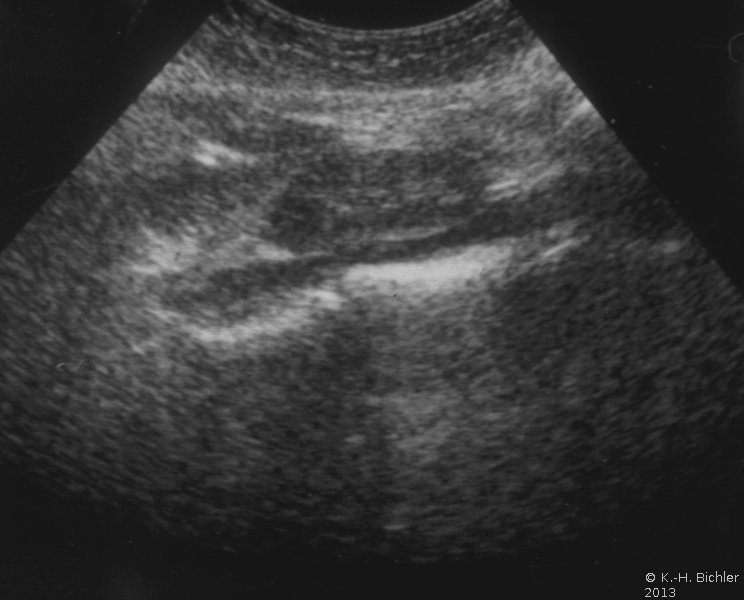

Die retrograde Sondierung gab Hinweis auf ein strangulierendes Hindernis im Bereich des Harnleiterabgangs (aberrierendes Gefäß, Bride?). Das retrograde Pyelogramm zeigte ein erweitertes, aber sonst unauffälliges NBKS (Abbildung 6).